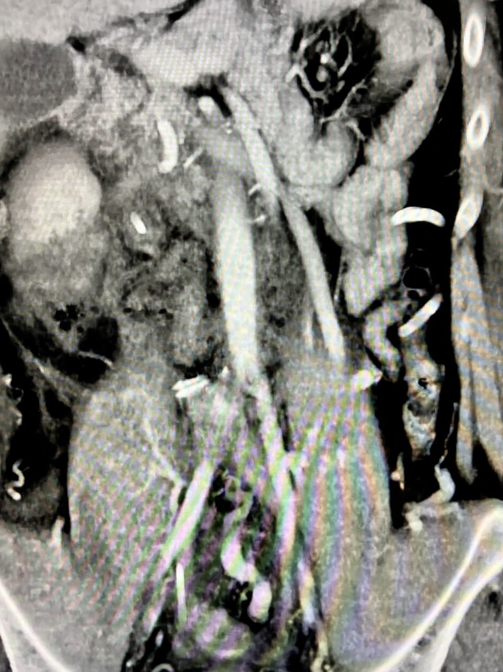

On re-evaluation with CT imaging after completion of chemotherapy, there was persistence of multiple necrotic-appearing left paravertebral and paracostal masses, which showed progression compared to the previous study.

Increase in size of the retroperitoneal nodal conglomerate, which encases and mildly compresses the aorta and collapses the inferior vena cava, with vascular infiltration not excluded.

The distal common iliac, external iliac, and right internal iliac veins are completely filled with hypodense material, consistent with deep vein thrombosis.

Grade II/IV right ureteropelvicalyceal dilatation secondary to obstruction of the proximal right ureter at the level of the nodal conglomerate.

The 3D reconstruction enabled:

- Assessment of the anatomical spaces and relationships of the masses

- Identification of the lumbar arteries and veins in close contact with the lesions

- Evaluation of the azygos and hemiazygos systems in terms of patency in the context of inferior vena cava collapse, as well as the relationship between the right ureter and the masses (Figure 3)